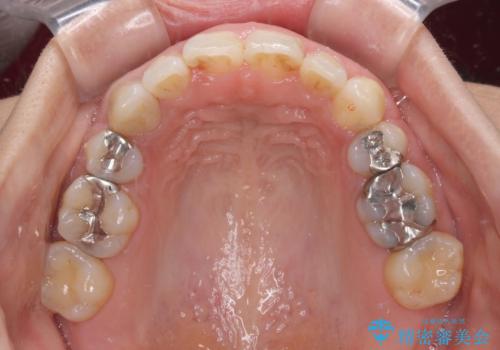

- 3年2ヶ月

- 上の前歯の捻じれと突出感を気にして来院された患者様です。

目立たない装置を希望とのことで、上顎左右第一小臼歯を抜歯し、インビザラインにて矯正治療を行うこととしました。